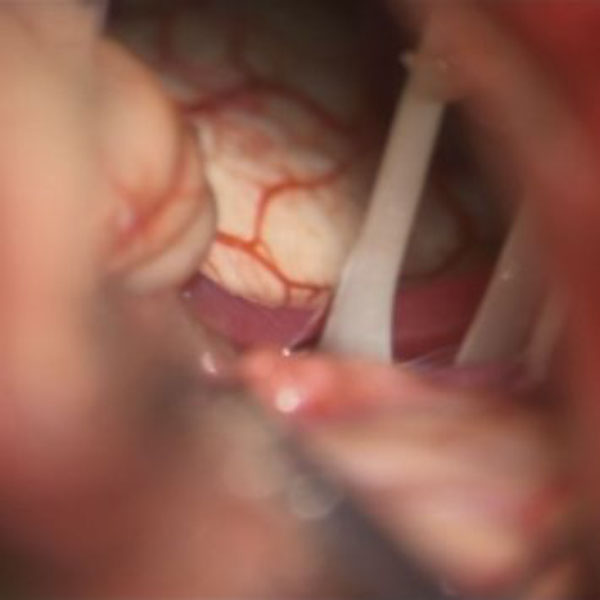

手術中

処置前